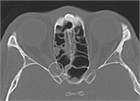

1. 造影CT(CTAngio)検査についてテキスト、画像を追加した。

1. 外傷性視神経損傷は直接外傷と間接外傷に分類され、原因として以下の6つがある。

1. ①視神経の挫滅または離断、②骨折による圧迫、③管内の出血による圧迫、④栄養血管の断裂、⑤瞬間的な骨のたわみによる障害、⑥管内における視神経の浮腫による圧迫